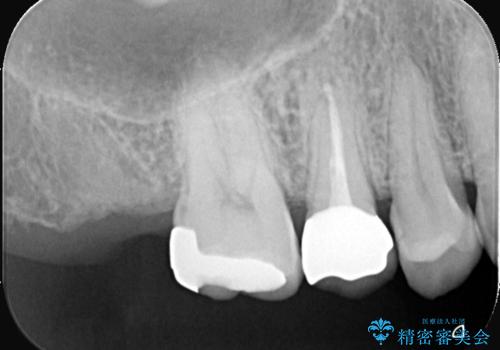

ラバーダムと顕微鏡を用いた根管治療を希望され、治療後は痛みも改善することができました。

その後、オールセラミッククラウンにて修復を行っています。

顕微鏡を用いて根管治療を行うことで、破折の有無などを判断しやすくなります。